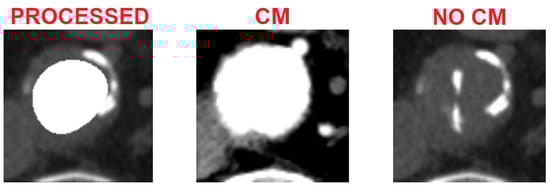

As an example, in Figure 14, there are the results of the processing of one of the 15 patients. On the left there is the basal image after the cropping process; only the aortic vessel needed to be highlighted, from which the patent lumen is to be extracted. At the center, instead, we have the reconstruction of the vessel using the SK and subsequent segmentation algorithms. Finally, on the right there are the related images with contrast medium, as reference. As can be seen, visually the algorithm is able to extract the patent area, with a fairly good degree of accuracy compared with the reference image. This is also confirmed by the trend of the error rates. In particular, the Dice Index (DCI), which measures the white pixels correctly classified by the algorithm, is on average greater than 0.82 (rounded), which indicates that the reference image (with the contrast agent) and the image extracted by the algorithm have a match greater than the 82%. A similar positive trend can be found for the Tanimoto Index (TI), which measures the ratio between correctly classified pixels and the total number of white pixels present both in the image extracted by the algorithm and in the reference one. The misclassification error ( E m ), which gives us a measure of misclassified pixels (occluded ones classified as pervious and vice versa), despite having been implemented in such a way that it conservatively estimates the lack of similarity between the two images, is on average no higher than 0.3 (rounded) and represents the complementary of TI. Finally, the bias index ( B p n ) mainly settles on negative values (average lower than −0.04), indicating that the algorithm tends to slightly underestimate the patency area, a characteristic that turns out to be positive from a clinical point of view, as it offers a more pessimistic assessment of the aneurysmal area.

Figure 14. Results of the entire sequence of one of the 15 patients processed. On the left, the basal CT images of the vessel (NO CM), on the right, the CT images of the vessel with the contrast medium (CM), in the center, the reconstructions with the extraction of the patent lumen (i.e., the processed image, C S K ). Next to each slice, we report some of the most significant errors (Dice Coincidence Index, Tanimoto Index, misclassification error and bias index).